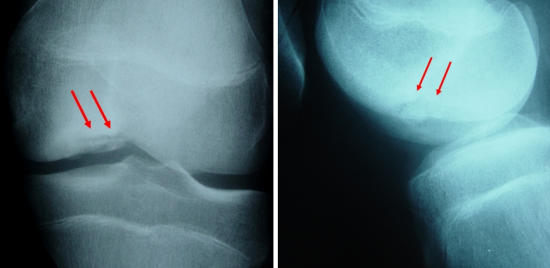

Orta yaştaki menisküs kök yırtıklarında tedavi yaklaşımı değişti

Menisküs yırtıkları, dizin en sık görülen sorunlarından birisidir. Genç hastalarda, bir şiddetli bir dönme hareketi veya darbe sonrası oluşan menisküs yırtıkları ile; ileri yaşta, basit bir çömelme veya halıya takılma sonrası oluşan yırtıkların farklı özellikleri vardır. Genç hastalarda oluşan yırtıklar, sağlam menisküste şiddetli bir zorlanma sonrasında ortaya çıkar ve genellikle cerrahi tedavi gerektirir.